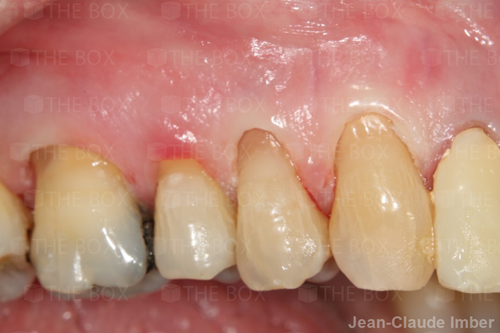

A new case was made public by Jean-Claude Imber check it out here.